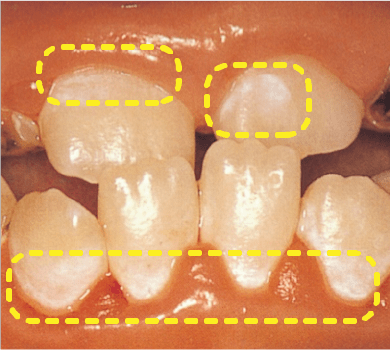

むし歯は、進行すると歯に穴があいてしまいます。その前段階で、エナメル質の内部からカルシウムやリンなどのミネラルが一部溶け出しているものの、歯の表層は保たれていて穴があく前の状態を「初期むし歯」と呼びます。

初期むし歯は、「ホワイトスポット」とも呼ばれ、表面が白く濁って見えることがあります。

この段階であれば、再石灰化によって健康な歯に戻すことが可能です。

しかし、いったん表層が崩れ歯に穴があいてしまうと、再石灰化による修復はできなくってしまいます。

- 写真提供 ライオン歯科材(株)